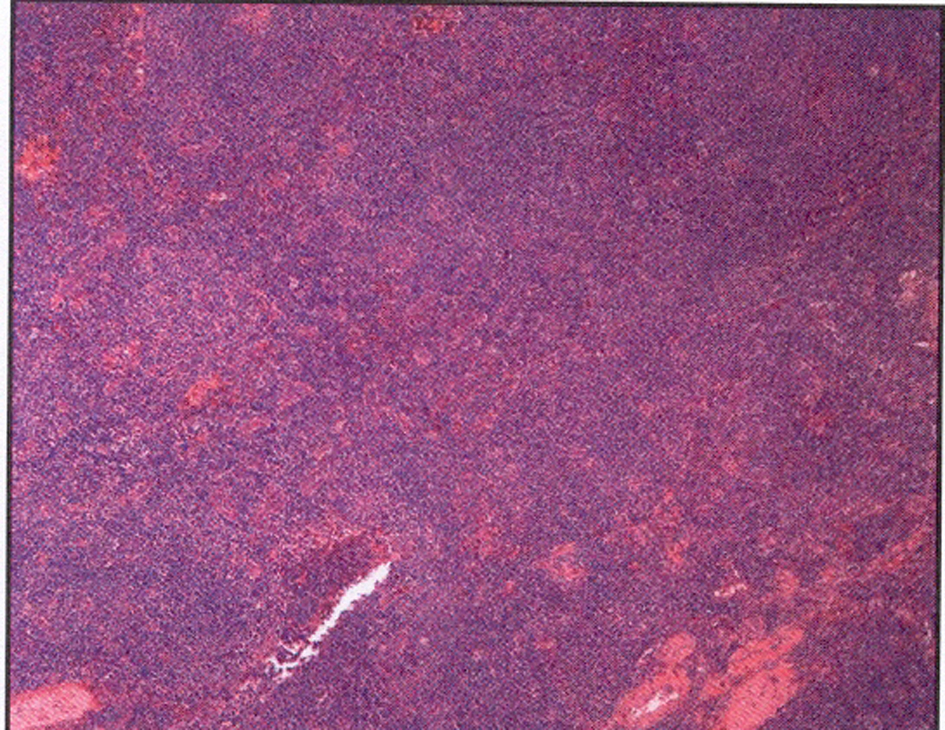

The left submandibular lymph node excisional biopsy and bone marrow biopsy were done. Pathological examination of the biopsy specimen of the lymph node revealed monotonous nodular infiltrate of small to medium sized lymphocytes with irregular nuclear contours, condensed chromatin, inconspicuous nucleoli and small to moderate amounts of cytoplasm, with noted follicular colonization (Fig. 2). Flow cytometry showed an expanded population of kappa-restricted CD19+ CD20+ CD23+CD5-CD10- B cells with unquantified CD5+CD10+ T cells. FISH analysis was negative for Ig H/BCL1 translocation, IgH/BCL2 translocation and for a MALT1 gene rearrangement. Pathological examination of the bone marrow revealed that hypercellular marrow (80%), and lymphoid aggregates that made up approximately 20% of the marrow cellularity and interstitial lymphoid aggregates. Flow cytometry performed on the bone marrow aspirate demonstrated an expanded population (10%) of kappa-restricted B cells that expressed CD19, CD20, CD45, HLA-DR but not CD5, CD10, CD103, CD11c. FISH analysis performed on bone marrow was positive for IgH rearrangement, while negative for IgH/BCL1 and IgH/BCL2 translocations and for ALK1 and BCL6 rearrangements.

![]() Click for large image | Figure 2. Left submandibular lymph node biopsy revealed a monotonous nodular infiltrate of small to medium sized lymphocytes with irregular nuclear contours with noted follicular colonization. |